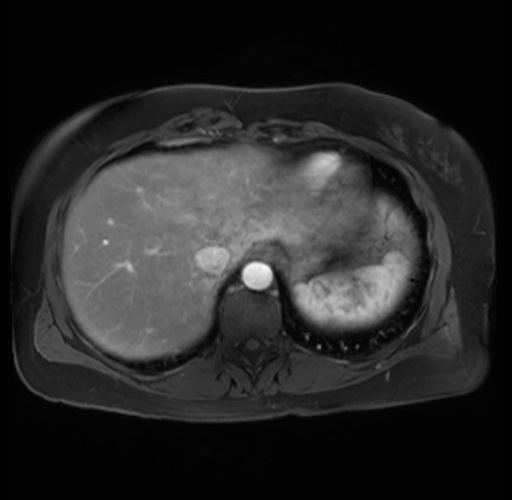

Imaging Analysis

Look through the patient's CT scan to identify any areas of concern for the necessary procedure.

Based on your CT findings, which issue(s) are present and would give reason for "planned slowing down moment(s)" in this case?

Considering a standard distal pancreatectomy procedure, what step(s) of the operation would you do differently in this case?